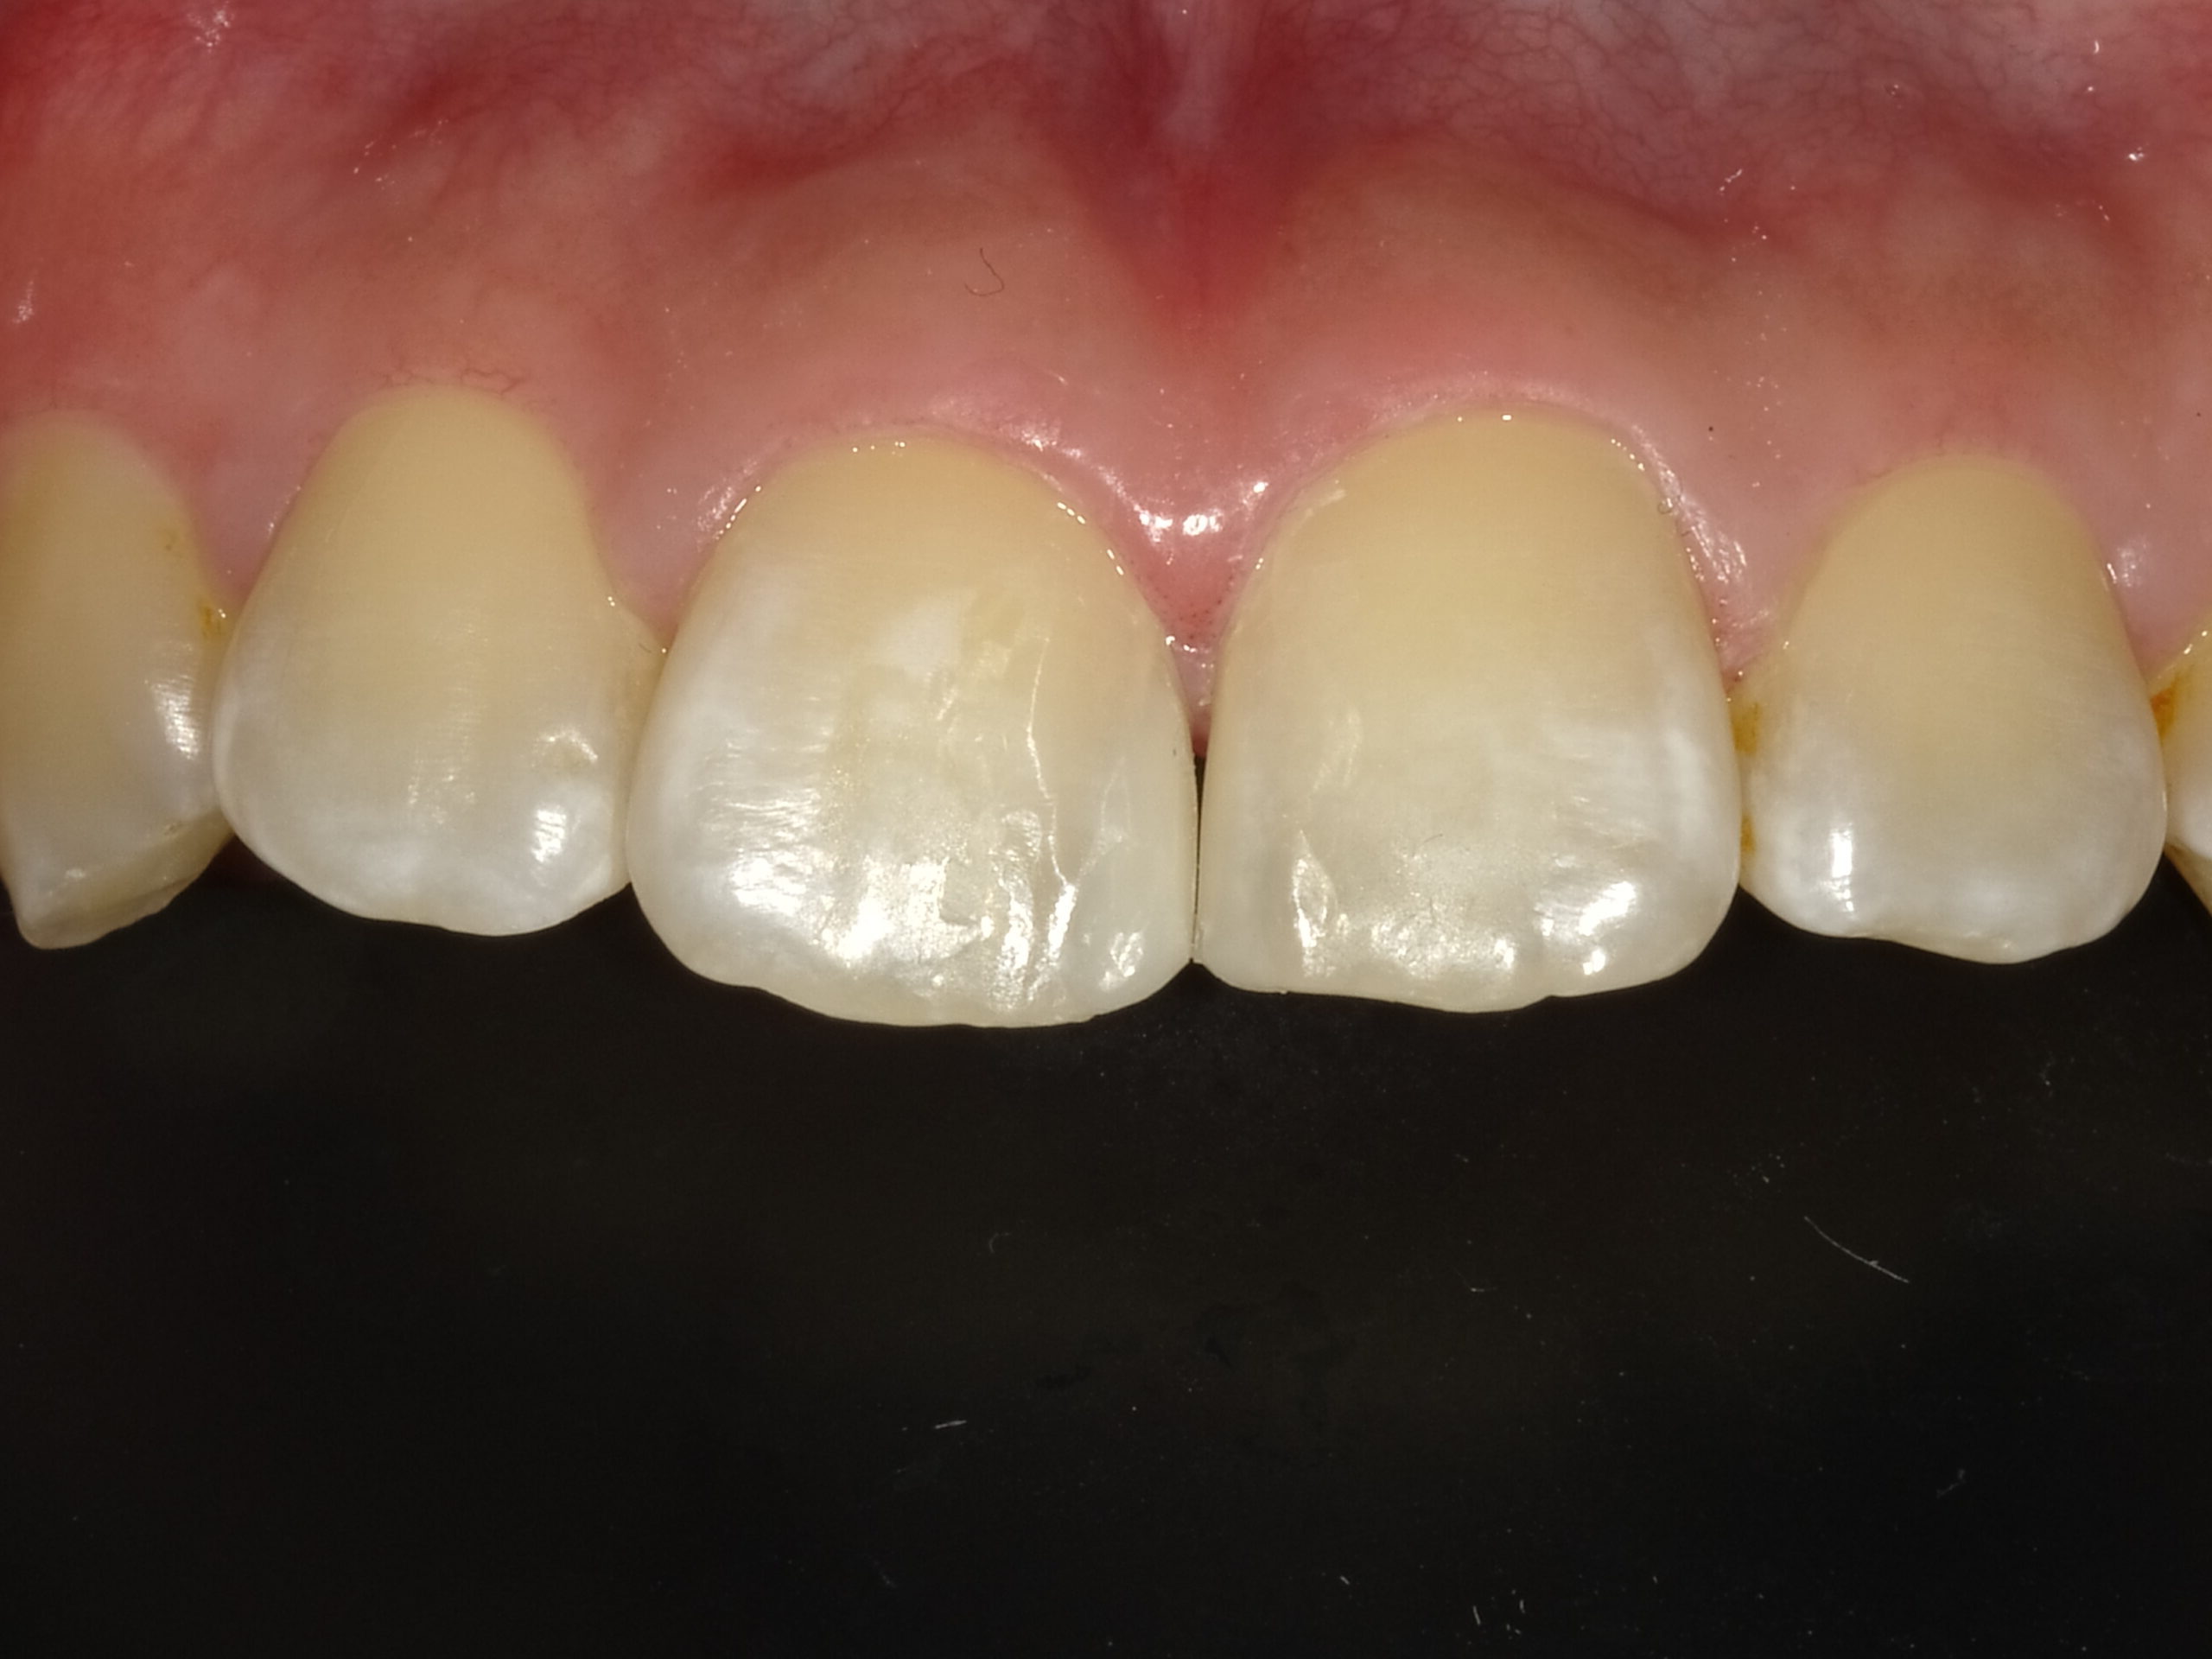

虫歯治療decay

審美歯科esthetic